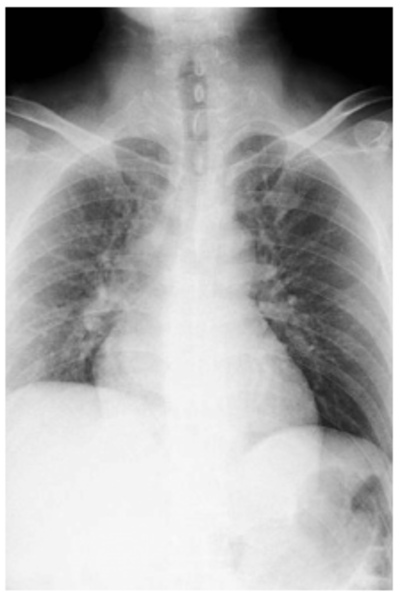

この双方の特性によって、レントゲン写真は[図表1]のように、X線が透過しづらい骨の部分が、白く映るのです。

[図表2]のように、X線は人体を直線的に透過した後に感光フィルムに達します。このとき人体の部位によってX線の透過度合い(吸収されやすさ)が異なることから、前述の通り、感光フィルムに達するX線にも強弱が現われ、その陰影がレントゲン写真に映し出されるのです。